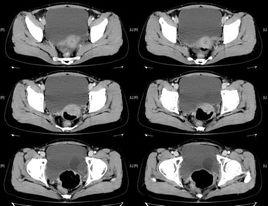

當輸尿管囊腫顯示為膀胱內邊緣光整的充盈缺損,有時需與膀胱腫瘤相鑑別,膀胱腫瘤充盈缺損邊緣不光滑、形態不規整,惡性腫瘤還有侵及膀胱壁的其他徵象。而B超、CT及MRI可以明確顯示含有尿液的囊腫。另外應與外傷、結石、炎症等阻塞輸尿管口,造成輸尿管遠端囊樣擴張所形成假性囊腫進行鑑別,此囊腫壁常不規則,周圍的透亮環寬窄不均,界限不清,可與之鑑別。

現如今常用的有三種方法:B超檢查、IVU檢查、膀胱鏡檢查,其中B超檢查是初診和篩選的首選方法,可以準確觀察到輸尿管囊腫在膀胱內的確切位置、大小和形態,於膀胱三角區的側方可以看見典型的圓形含液性光環,隨輸尿管蠕動呈明顯的周期性增大和縮小。IVU檢查是最基本的檢查方法,可以觀察到腎臟、輸尿管、膀胱情況,了解泌尿系有無畸形、功能障礙,輸尿管囊腫內充盈造影劑時呈典型的“眼鏡蛇”樣特徵性表現,排尿期膀胱造影更是觀察有無輸尿管返流的主要方法。膀胱鏡檢查可以直接觀察到膀胱內情況,但是由於個別輸尿管囊腫可以隨膀胱內壓增加而變小,甚至可以完全消失,所以,在用膀胱鏡觀察時一定要注意進水的多少,避免膀胱內壓力過高而致囊腫消失,造成漏診。